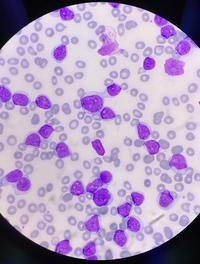

Les syndromes myélodysplasiques (SMD) constituent un groupe hétérogène d’hémopathies caractérisées par une dysplasie de la moelle osseuse [...]

Les syndromes myélodysplasiques (SMD) de faible risque correspondent aux catégories risque faible et risque intermédiaire 1 de l’IPSS [...]